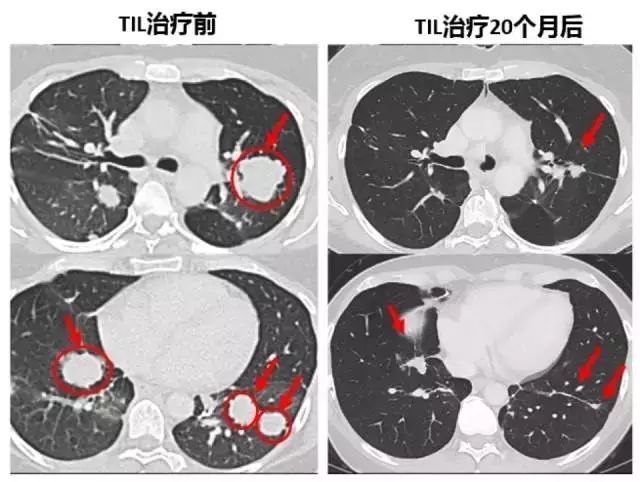

转移性结直肠癌患者肿瘤患者经过TIL细胞疗法治疗后,7个肺部的转移灶在几周后都变小乃至消失!

22个月后,这名患者的肿瘤(黄色箭头)消失得无影无踪(图片来源:《Nature Medicine》)